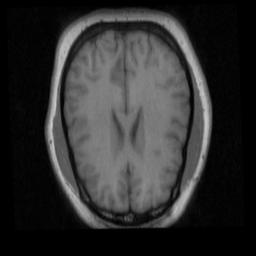

Figure 9 illustrates the registration results of unsupervised methods w/ mask (in Table V) and without mask (in Table III).

Refer to caption

Figure 9: Illustration of the liver registration performance of the proposed unsupervised methods with and without mask: (a), (c), (e), (g), (i) and (k) respectively denote the moving images warped by PN, PE, PE with more unlabeled data, PMN w/ mask and PME w/ mask, PME w/ mask with more unlabeled data. The translucent red masks in (b), (d), (f), (h), (j), (l) respectively correspond to (a), (c), (e), (g), (i), (k) and denote the warped ground truth segmentation mask of the moving images. The white masks in (b), (d), (f), (h), (j), (l) are the ground-truth segmentation mask of the fixed image. The red and yellow crosses denote landmarks of moving image and fixed image, respectively.

The unsupervised methods PMN w/ mask and PME w/ mask exhibit capability to align object boundaries by achieving high Jaccard Coefficient 0.903 and 0.905 respectively. And it’s evidenced that ROI segmentation mask has significantly increased the performance of liver registration both in Dist and Jacc. Notably, methods based on convolution neural networks achieve 100x speedup compared to traditional methods. Figure 7 illustrates the registration results of different methods on liver CT data.